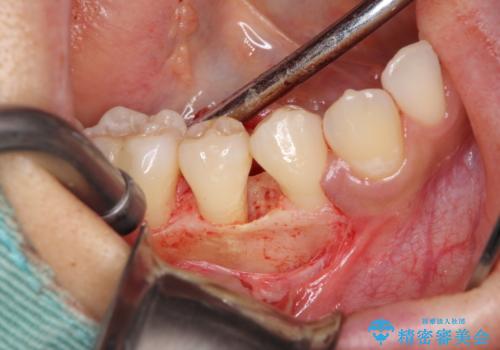

患者様は、他院で右下の歯を抜歯かもと言われました。全体の歯周病はなく、右下の1歯だけ骨が極端に減少していました(初診時歯周ポケット7mm。通常は3mm以下。)。その歯だけ咬合が強いことが原因と考えられたため、咬合を弱くする処置と減少した骨を再生する処置が必要になりました。

骨の再生治療手術をして10か月経過観察をしたのち、骨を平坦化する手術を行い、治療終了となりました。